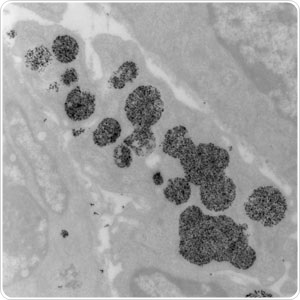

Shown here at 9900x magnification, tumor cells readily take up magnetic nanoparticles (black objects). When a tumor containing nanoparticles is exposed to an alternating magnetic field, the nanoparticles will heat and kill the tumor cells.

This evolving treatment approach involves the injection of nanoparticles into the tumor, which are then activated with magnetic energy. Once activated the nanoparticles produce heat inside the cancer cell. The heat kills the cancer cell with minimal damage to surrounding tissue.